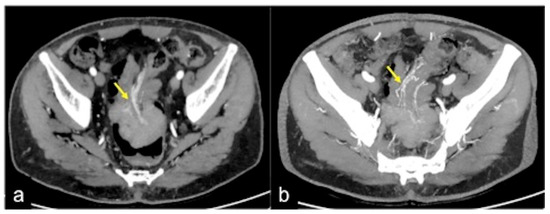

| Rectal Varices and Haemorrhoids (Figure 35) | Pain and/or bleeding. | Dilated veins with possible bleeding visible in the portal phase; rectal varices are located proximal to the linea dentata while haemorrhoids are located in the anus. |